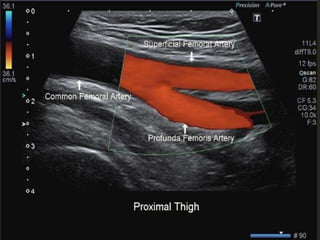

⦁ The bifurcation of the common femoral artery into the

profunda femoris and superficial femoral arteries is then

examined using colour and spectral Doppler.

⦁ The common femoral artery runs from the inguinal ligament

to its division into superficial and deep femoral arteries in the

upper thigh; this division is usually 3–6 cm distal to the

inguinal ligament.

⦁ The deep femoral artery, or profunda femoris artery, passes

posterolaterally to supply the major thigh muscles.

⦁ The importance of the profunda femoris lies in its role as a

major collateral pathway in patients with significant

superficial femoral artery disease.

⦁ The superficial femoral artery (also referred to as the femoral

artery) passes downwards along the anteromedial aspect of

the thigh lying anterior to the vein; in the lower third of the

thigh it passes into the adductor canal.